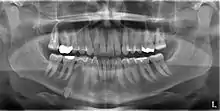

Mandibular canine impacted in the chin

An impacted tooth is one that fails to erupt into the dental arch within the expected developmental window. Because impacted teeth do not erupt, they are retained throughout the individual's lifetime unless extracted or exposed surgically. Teeth may become impacted because of adjacent teeth, dense overlying bone, excessive soft tissue or a genetic abnormality. Most often, the cause of impaction is inadequate arch length and space in which to erupt. That is the total length of the alveolar arch is smaller than the tooth arch (the combined mesiodistal width of each tooth). The wisdom teeth (third molars) are frequently impacted because they are the last teeth to erupt in the oral cavity. Mandibular third molars are more commonly impacted than their maxillary counterparts.

Classifications enable the oral surgeon to determine the difficulty in removal of the impacted tooth. [9] The primary factor determining the difficulty is accessibility, which is determined by adjacent teeth or other structures that impair access or delivery pathway. The majority of classification schemes are based on analysis on a radiograph. The most frequently considered factors are discussed below.